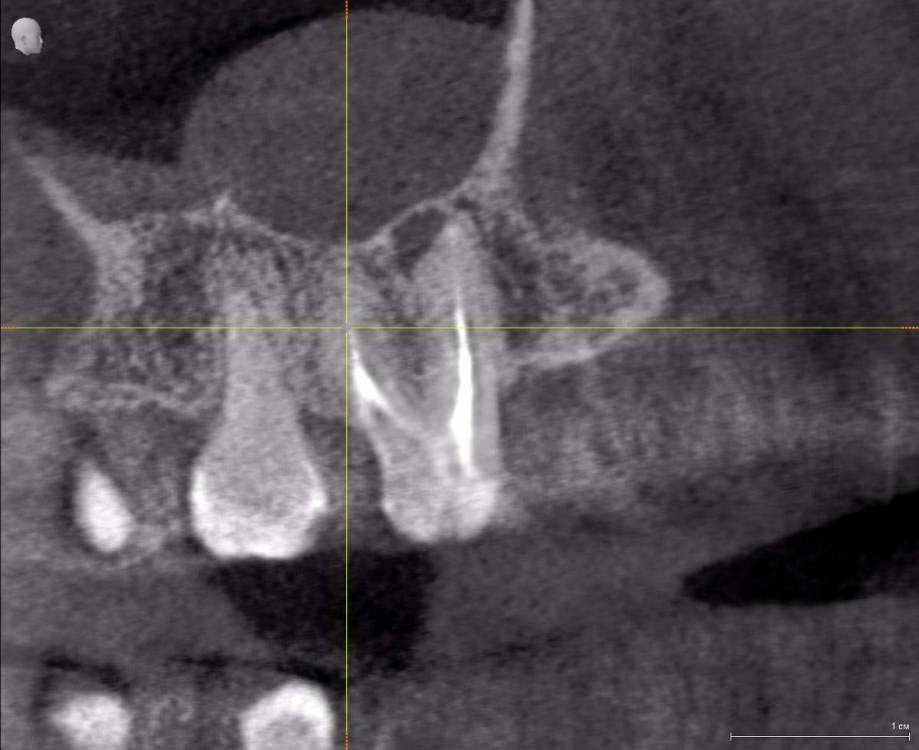

Алексей82 Опубликовано 9 февраля, 2022 Поделиться Опубликовано 9 февраля, 2022 Здравствуйте. Подскажите пожалуйста надо ли чистить правый канал? Врач говорит что он чуть не до чищен, но гарантий что будет лучше или хуже никто не даёт. Зуб не беспокоит. Коронки пломба стоит больше 10 лет. Сейчас надо поменять корону, т. к. снизу ставлю имплант, а верхняя коронка выдвинулась. Доктор говорит, когда будет стоять имплант возрастёт нагрузка на верхний зуб и могут быть неприятности, а может и не быть. За чистку каналов тоже говорят, что возможна перфорация или это в трудно доступный канал - принимай решение сам. Стоит ли туда лезть? Ссылка на комментарий

Алексей82 Опубликовано 10 марта, 2022 Автор Поделиться Опубликовано 10 марта, 2022 Здравствуйте. Вот ссылка на КТ. Посмотрите пожалуйста. Или может надо было скрин сделать чегото. https://dropmefiles.com/zxr3f Ссылка на комментарий

wladdX Опубликовано 10 марта, 2022 Поделиться Опубликовано 10 марта, 2022 (изменено) Попробовать поработать в корневых каналах можно, насколько это будет успешно, сказать невозможно. Изменено 10 марта, 2022 пользователем wladdX 1 1 Ссылка на комментарий